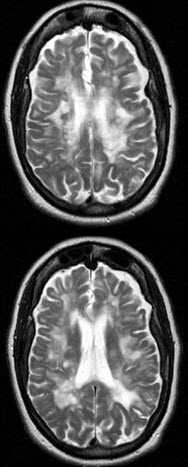

女,56岁,既往有癫痫病史,请结合CT图像选择最可能的诊断( )

A:多发性硬化

B:脑出血

C:脑梗死

D:颅脑肿瘤

E:正常脑实质